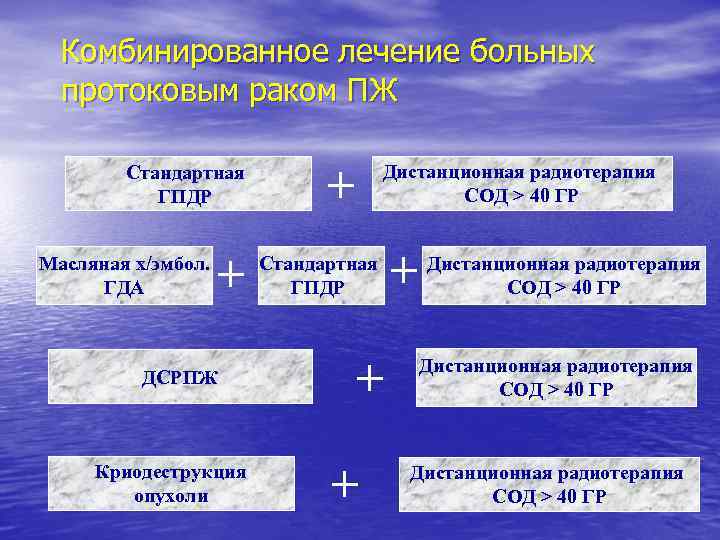

Комбинированное лечение больных протоковым раком ПЖ Стандартная ГПДР Масляная х/эмбол. ГДА + ДСРПЖ Криодеструкция опухоли + Дистанционная радиотерапия СОД > 40 ГР Стандартная ГПДР + + + Дистанционная радиотерапия СОД > 40 ГР

Комбинированное лечение больных протоковым раком ПЖ. Стандартная ГПДР Криодеструкция опухоли + + Дистанционная радиотерапия СОД 40 – 66 ГР Дистанционная радиотерапия СОД 40 – 98 ГР